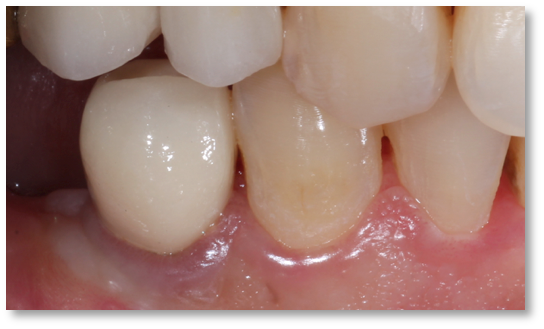

![]() | ![]() |

| Untreated severe gum disease | Gum disease treated and stabilised by Dr Halai |